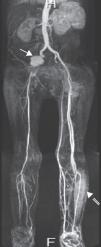

Caso clínicoDoente do género masculino, de 50 anos de idade, com antecedentes médicos de tabagismo, toxicodependência e hepatite C crónica, recorreu ao serviço de urgência por astenia, febre e cefaleia com um mês de evolução e dor abdominal desde há 2 dias. Ao exame objetivo o doente apresentava febre e a auscultação cardíaca evidenciou um sopro diastólico agudo, em decrescendo, grau iii/vi, ao nível do bordo esquerdo do esterno. O doente não apresentava sinais de insuficiência cardíaca. O estudo analítico demonstrou insuficiência renal aguda (Cr 2,5mg/dl, Ureia 60mg/dl, valores normais em análises efetuadas uma semana antes), elevação da proteína c-reativa (77,5mg/L) e anemia normocítica e normocrómica (Hb 11,2g/dl). Realizou tomografia computorizada (TC) abdominal que evidenciou esplenomegalia, não se visualizando áreas de enfarte, e hidroureteronefrose direita condicionada por aneurisma da artéria ilíaca comum direita com 42mm de maior diâmetro. Efetuado ecocardiograma transtorácico no qual se observou uma vegetação de 15mm na cúspide não coronariana da válvula aórtica (Figura 1) e insuficiência aórtica severa (Figura 2), com compromisso moderado a grave da função sistólica do ventrículo esquerdo (fração de ejeção de 35%), achados confirmados por ecocardiograma transesofágico. O doente foi internado no Serviço de Cardiologia, tendo iniciado antibioterapia empírica com vancomicina e meropenem. Foi decidido não introduzir aminoglicosídeo atendendo à taxa de filtração glomerular baixa, estimada em 20ml/min/1,73m2. No 2.° dia de internamento verificou-se lentificação cognitiva do doente, sem alterações neurológicas focais, tendo-se requisitado ressonância magnética (RM) cerebral, na qual foi possível observar múltiplos enfartes cerebrais recentes. As hemoculturas isolaram Candida albicans (C. albicans) sensível à anfotericina lipossómica, tendo-se iniciado terapêutica antifúngica e contactado o centro cirúrgico no sentido de transferir o doente para substituição valvular aórtica. Enquanto aguardava transferência, o doente iniciou dor súbita intensa no membro inferior esquerdo, com arrefecimento e perda de pulsos, constituindo um quadro de isquemia aguda do membro, de provável causa cardioembólica (vegetação micótica). Foi transferido para o centro de cirurgia vascular com urgência, onde realizou tromboembolectomia arterial femuro-distal esquerda. Posteriormente foi transferido para o centro de cirurgia cardiotorácica onde se procedeu à substituição da válvula aórtica por prótese biológica. O exame microbiológico da válvula aórtica e do êmbolo retirado da artéria femoral esquerda demonstraram crescimento de C. albicans. O ecocardiograma transtorácico pós-operatório evidenciou prótese aórtica normofuncionante, tendo sido transferido para o Serviço de Cardiologia deste hospital 14 dias depois. Durante o internamento apresentou febre e subida dos marcadores de inflamação. Repetiu o ecocardiograma transtorácico que confirmou a presença de prótese normofuncionante, sem evidência de vegetações. Realizou angio-ressonância magnética abdominal e dos membros inferiores, tendo sido identificado: volumoso pseudoaneurisma do eixo arterial ilíaco direito com oclusão da artéria ilíaca externa distal ao pseudoaneurisma; múltiplas tumefações compatíveis com abcessos na região inguinal e coxa esquerdas (local da abordagem cirúrgica vascular prévia); e abecedação do compartimento muscular ântero-lateral da perna esquerda (Figura 3). Atendendo à existência de foco infeccioso e ao ecocardiograma transtorácico sem evidência de endocardite, decidiu-se não repetir o ecocardiograma transesofágico. O paciente foi transferido para o Serviço de Cirurgia Vascular, tendo sido submetido a tratamento cirúrgico: aneurismectomia total com realização de pontagem femuro-femoral cruzada esquerda-direita com veia grande safena direita invertida, associado a exploração e drenagem dos abcessos na coxa e na perna esquerdas. O exame microbiológico do pseudoaneurisma evidenciou crescimento de Staphylococcus epidermidis (S. epidermidis). Durante o internamento no Serviço de Cirurgia Vascular o doente manteve febre intermitente e deterioração progressiva do estado geral. Repetiu hemoculturas que demonstraram crescimento de S. epidermidis, tendo iniciado antibioterapia de largo espectro com vancomicina e meropenem. Realizou TC pélvico e das coxas identificando-se 2 novos pseudoaneurismas: na artéria ilíaca interna esquerda e na artéria femoral superficial esquerda. O paciente foi novamente submetido a tratamento cirúrgico: durante o procedimento constatou-se a rápida progressão da situação clínica, havendo rotura do pseudoaneurisma femoral esquerdo, com extensa infiltração hemorrágica e abcedação da coxa. Procedeu-se a laqueação das artérias ilíaca interna esquerda e femoral superficial esquerda, associado a desbridamento alargado de tecidos desvitalizados e de coleções purulentas. Em tempo cirúrgico deferido procedeu-se a amputação transfemoral aberta, por ter havido progressão para gangrena da perna. Durante o internamento prolongado no Serviço de Cirurgia Vascular, de cerca de 4 meses, o doente manteve sempre terapêutica antifúngica e foi submetido a reamputação transfemoral e a vários desbridamentos cirúrgicos de abcessos do coto. Após o encerramento parcial do coto o doente obteve alta, clinicamente estável, tendo-se decidido não manter antifúngico devido à hepatite C crónica que o doente apresentava e à possível toxicidade hepática dos antifúngicos.

Cerca de 4 meses após a alta, o doente foi admitido no serviço de urgência por febre e dor abdominal. Realizou TC abdominal que evidenciou múltiplos enfartes renais e esplénicos e trombo/êmbolo no tronco celíaco (Figura 4). Realizou ecocardiograma transtorácico que demonstrou vegetação de 8mm ao nível da prótese aórtica e insuficiência aórtica moderada. Foi transferido para o centro de cirurgia cardiotorácica para cirurgia emergente, tendo apresentado paragem cardiorrespiratória antes de entrar no bloco. As hemoculturas que o doente realizou no serviço de urgência evidenciaram crescimento de C. albicans.